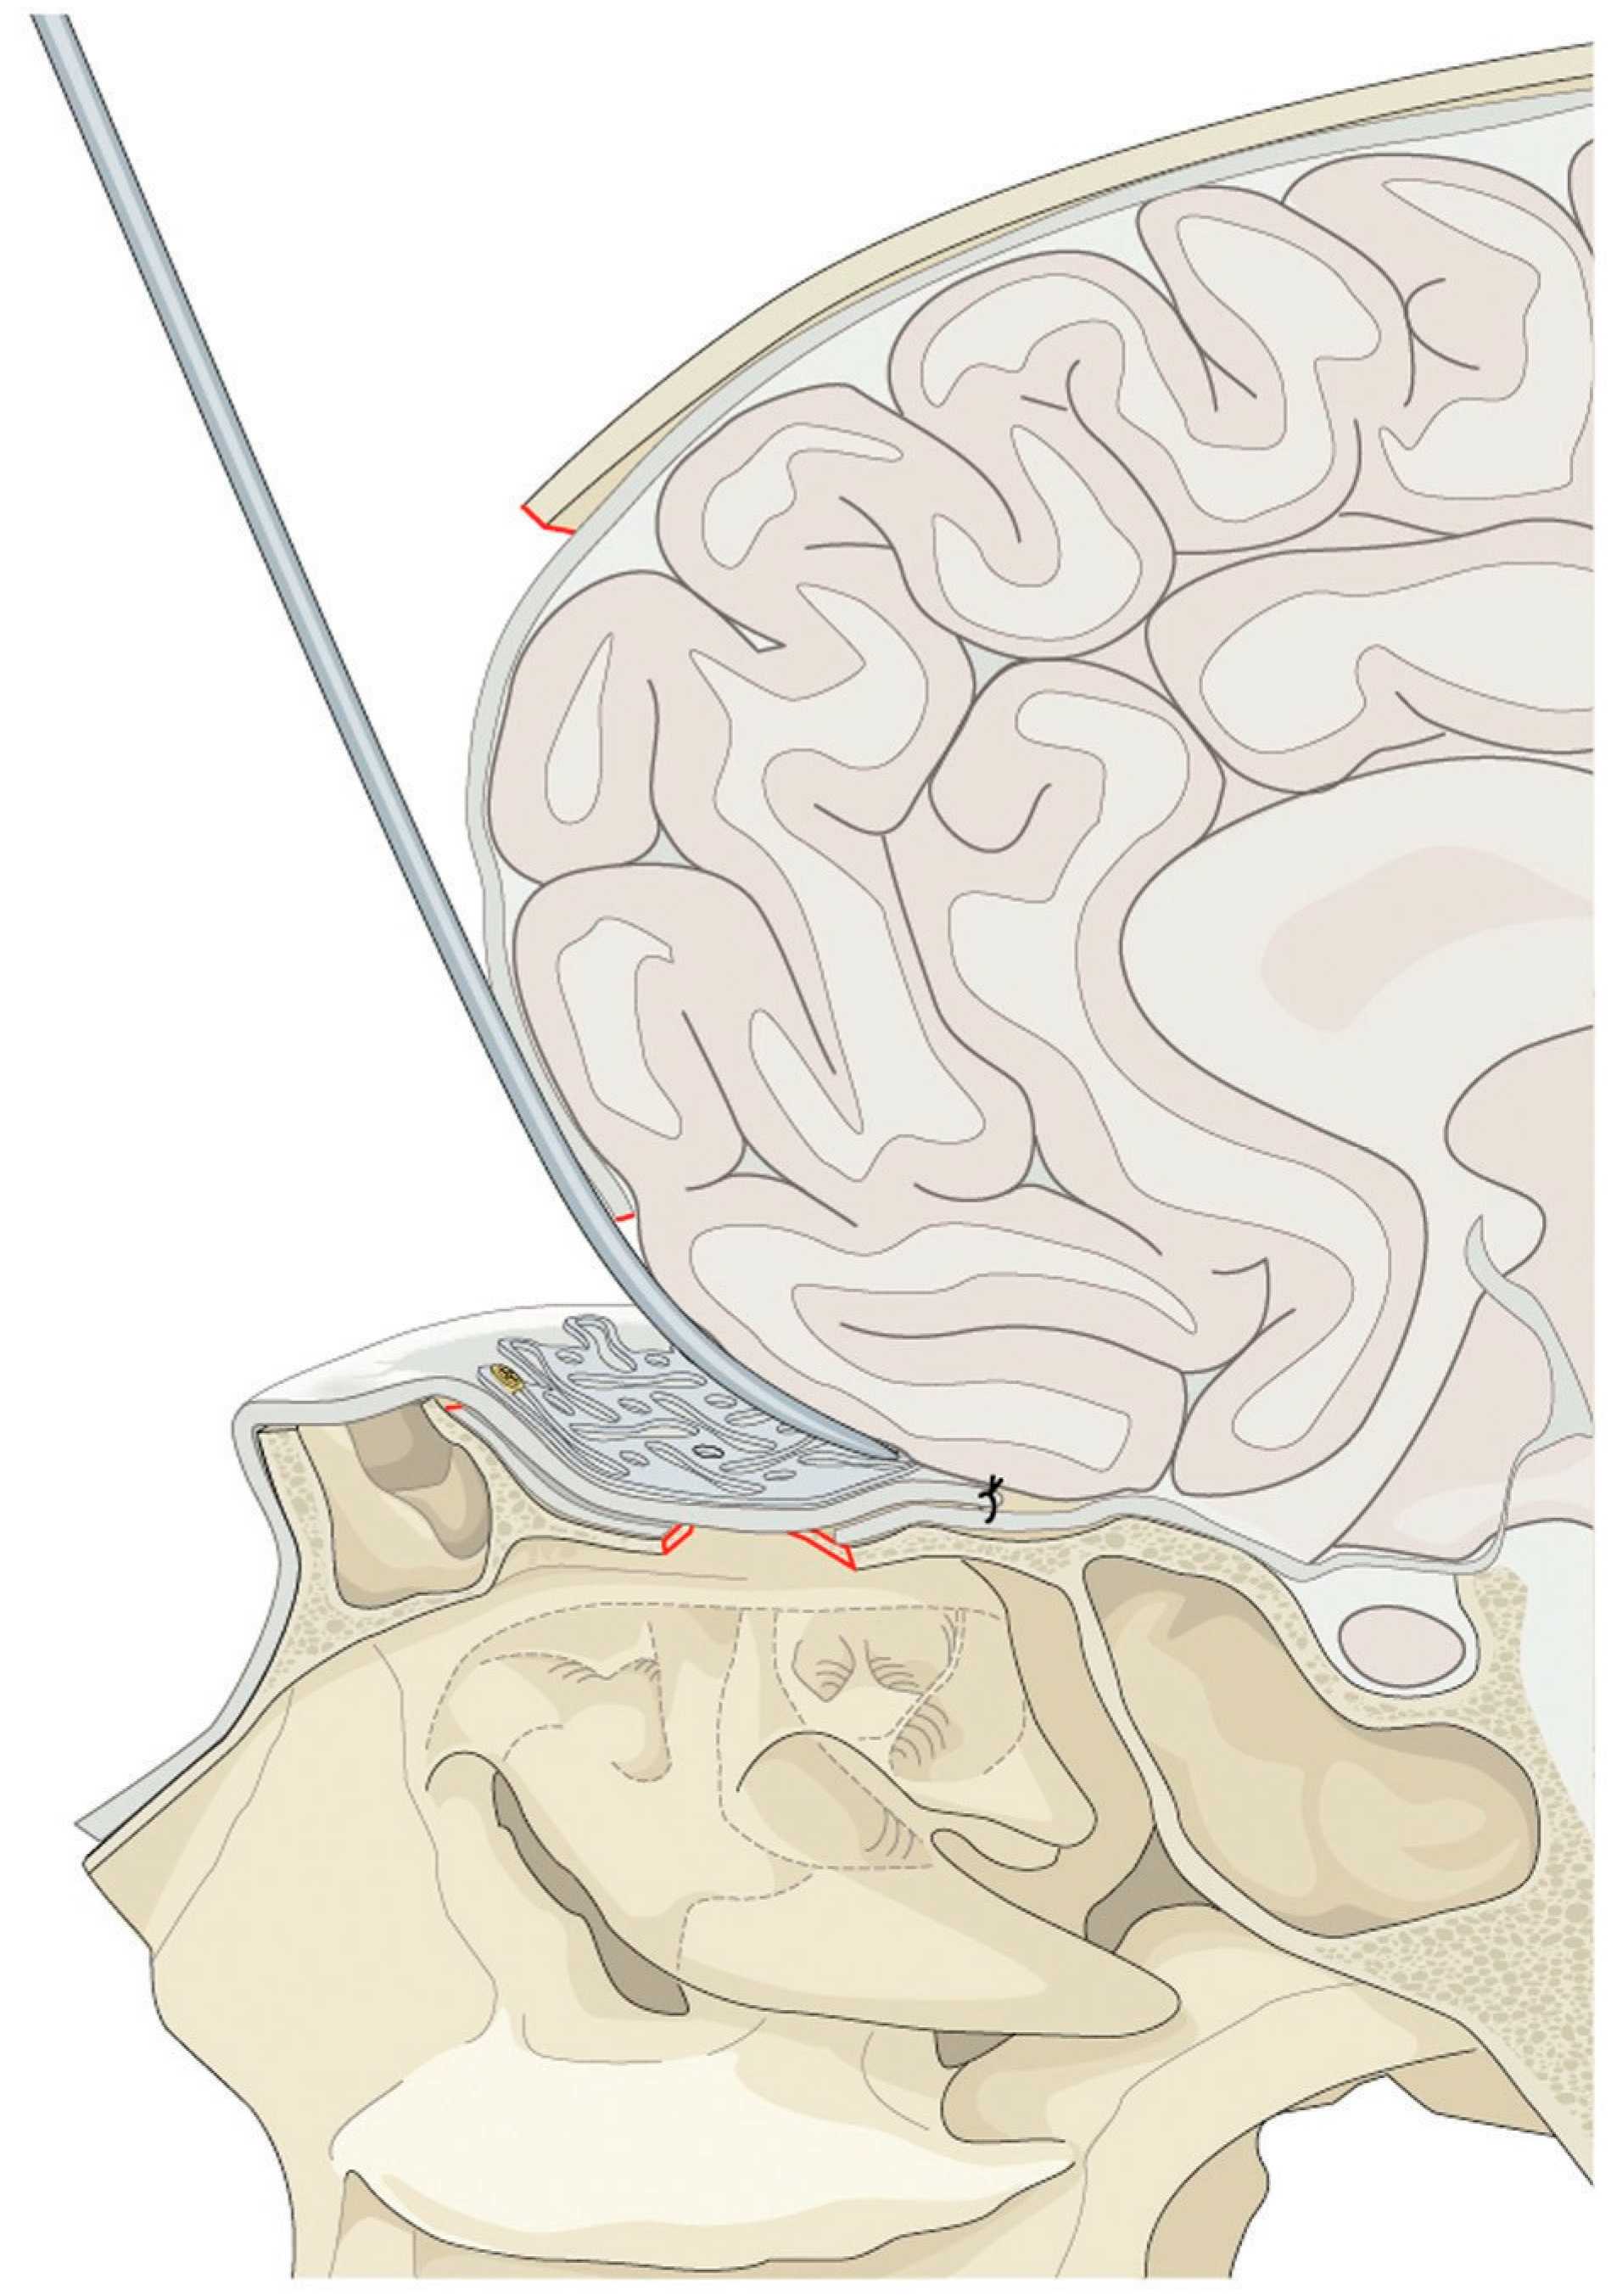

Faced with this diagnosis and due to a large bilateral bone defect, another surgery was proposed to reconstruct the bone defect and reduce the protrusion of the brain using “sandwich” technique (Figure 6a). This technique aims to cover the defect and reinforce the anterior cranial base using local or free flaps with a tailored piece of titanium mesh, respectively.

Before the second procedure, the dimensions of bone defect were measured using 3D computer software and the titanium mesh contoured for a more accurate implant (Figure 6b). Thus, the operation was planned as shown in Figure 7. The planned reconstruction started with the same steps of the first procedure. Then, the contoured mesh was placed over the anterior skull base defect with the help of 4-mm screws (Figure 8a,b).

Figure 6. (a) The planning of the reconstruction included the placement of a pericranial flap (red layer) on the defect, the titanium mesh (blue layer). (b) The titanium mesh was contoured previously for a more accurate implant.

Figure 7. The pericranial flap is brought in to reline the bone defect of the anterior skull base. The flap should be sutured to the dura to eliminate dead space. The titanium mesh is placed with a screw on the frontal bone over the pericranial flap to reinforce the reconstruction.